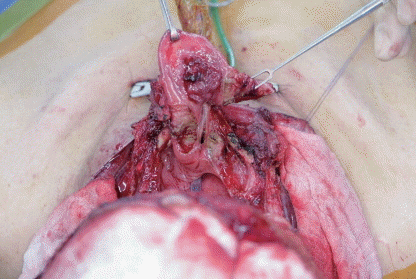

방사선치료 후 재발한 성문상부의 악성종양을 절제하기 위해 다음과 같이 원발병소 절제술 및 경부임파선 절재술을 시행하였다. 상기 술식에 대한 설명 중 옳지 않은 것은?

① 종양이 성문 상부를 넘어서 편측 구인두를 1 cm 정도까지 침범하였을 확장(extended) 술식을 적용할 수 있다.

② 피열연골의 점막을 침범하였을 경우에는 편측의 피열연골을 같이 제거할 수 있다.

③ 방사선치료 후 재발 환자나 고령, 폐기능 장애가 있는 환자에서도 안전하게 시행할 수 있다.

④ 술식을 확장할 경우에도, 적어도 하나의 피열후두주름, 피열연골, 편측의 갑상연골과 윤상연골이 있어야 시행가능하다.

⑤ 종양이 전연합부, 갑상연골 또는 윤상연골에 파급되었을 경우를 수술의 적응증이 되지 않는다.

답 ③

해 설 폐기능이 좋지 않아 기침이 어렵거나 뇌병변으로 인해 수술 후 재활이 어려울 경우는 환자와 보호자, 그리고 의료진과의 충분한 의사 소통을 통해 술식을 결정하는 것이 좋다.